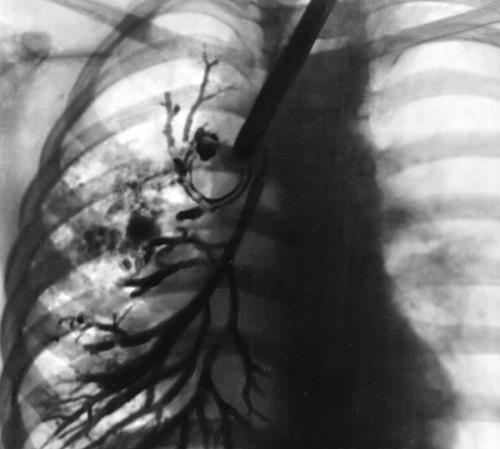

Кеуде қуысының рентгенограммасы

Бронхография:

Бронхографияда деформация, бронхтардың жақындауы, олардың цилиндрлік кеңеюі, бронхоэктаздан дистальды орналасқан бронх тармақтарыны контрасталмауы анықталды.